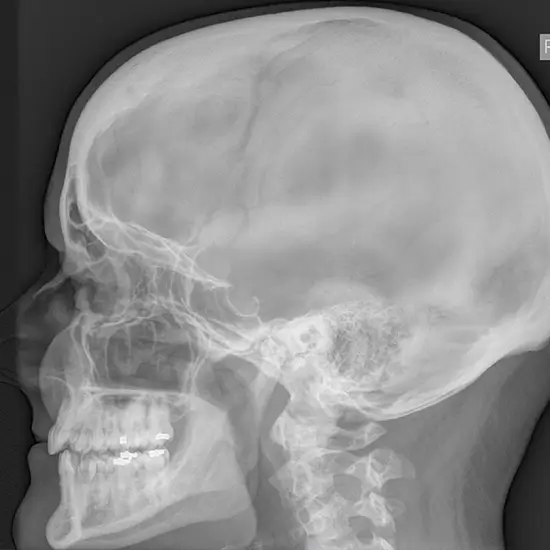

X-Ray Left Mastoid LAT/Oblique

The Mastoid X-ray test is used to visualize the mastoid, a skull bone located just behind the ear. This bone is composed of air-containing spaces and cells that aid ear drainage and hygiene.